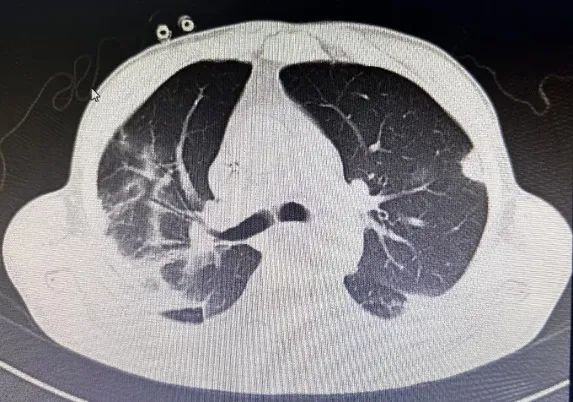

经积极抗感染治疗,患者仍持续处于稽留热,体温最高达39.8℃,并逐渐出现胸闷、气短症状伴有咳嗽、咳痰。右肺中下叶可闻及少量散在湿啰音及胸膜摩擦音。感染指标持续上升,复查肺部CT提示:双肺多发感染性病变,较前进展。

调整治疗后,患者病情仍未见好转并逐步恶化,遂转入ICU继续治疗。在我院ICU予以无创呼吸机通气,为了明确病因,行支气管镜检查取样成功,结果显示:鹦鹉热衣原体。结合血常规、CRP和胸部CT检查以及他饲养鸟类动物病史,此时就明确了,原来患者这次是鹦鹉热衣原体引起的肺部感染——俗称“鹦鹉热”。

重症鹦鹉热患者可于短期内出现呼吸衰竭和ARDS等呼吸系统症状。胸部CT检查以炎性病变始于单侧肺下叶多见,加重后累及双侧肺叶,上下肺均可受累,可合并有小片状的磨玻璃影、结节影、实变影和小叶间隔增厚,以胸膜下分布为主,常见“支气管充气征”、“细网格征”,可见“晕征”,常伴有胸腔积液,可伴有肺门及纵隔淋巴结肿大。治疗上常用的Cps抗菌药物包括四环素类、新型四环素类衍生物、大环内酯类和氟喹诺酮类等药物。